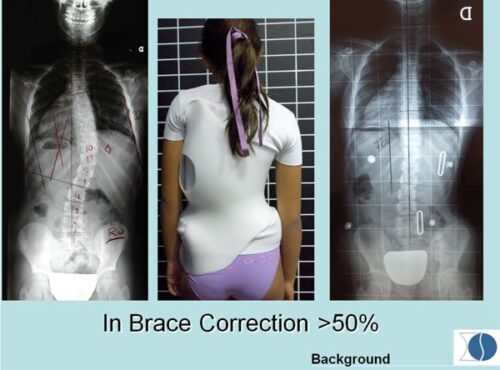

يُعد اعوجاج العمود الفقري مجهول السبب عند المراهقين (Adolescent Idiopathic Scoliosis – AIS) من أكثر اضطرابات العمود الفقري شيوعًا في مرحلة النمو، ويُعتبر العلاج بحزام اعوجاج العمود الفقري (Brace) الطريقة التحفظية الأكثر استخدامًا لتصحيح الانحناء ومنع تفاقمه.

يُستخدم حزام اعوجاج العمود الفقري كخيار علاجي غير جراحي لتقليل درجة الانحناء ومنع تزايده أثناء فترة النمو السريع.

يتم تصميم الحزام بشكل مخصص لكل مريض بناءً على زاوية الاعوجاج (زاوية كوب)، ومكان الانحناء، وسن المريض، ومستوى نمو العظام.

ويُنصح باستخدام الحزام خصوصًا عندما تكون زاوية الانحناء بين 20 و40 درجة، ولم يكتمل بعد النضج العظمي.

ويتم تقييم النتائج بشكل دوري من خلال الأشعة السينية لقياس زاوية الانحناء (زاوية كوب).

إذا أظهرت المتابعة أن الانحناء لم يتفاقم، فهذا يعني أن العلاج بالحزام ناجح، ويستمر حتى اكتمال النمو العظمي.

التصميم المريح والجذاب لحزام اعوجاج العمود الفقري يساعد على زيادة رضا المريض والتزامه بالعلاج.

تخفيف الوزن وتحسين المواد المستخدمة في صناعة الحزام يُقلل من الشعور بعدم الراحة.

التطور الكبير في تصميم الأحزمة الطبية جعل علاج اعوجاج العمود الفقري عند المراهقين أكثر نجاحًا وأقل إزعاجًا. باستخدام تقنيات التصوير الثلاثي الأبعاد والمحاكاة الرقمية، أصبح الحزام أكثر خفة وراحة، ويعطي نتائج أفضل في تصحيح الانحناء والتواء العمود الفقري.